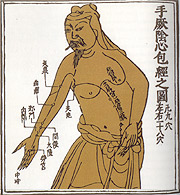

相传远古时代有两位传奇人物,黄帝与炎帝(又名神农)。历史学家虽不能确定他们是否真正存在,但可以确定他们的年代大概是公元前2500-2700年。两人都被认为是中医药始祖之一,对中医药贡献良多。

相传远古时代有两位传奇人物,黄帝与炎帝(又名神农)。历史学家虽不能确定他们是否真正存在,但可以确定他们的年代大概是公元前2500-2700年。两人都被认为是中医药始祖之一,对中医药贡献良多。 商人民居住在中国境内的黄河盆地,被认为是中国早的祖先之一。他们行医的方式非常原始,往往将迷信、传说及治疗经验结合应用。据当时出土的水牛及乌龟甲骨文记载,已有数种疾病的描述和治疗方法,人们更以酒及热水作药物,利用针及青铜刀作手术用具。相传以汤液治病始自此期。

中医指中国传统医学,它承载着中国古代人民同疾病作斗争的经验和理论知识。是我国一项民族文化遗产。它是在古代朴素的唯物论和自发的辨证法思想指导下,通过长期医疗实践逐步形成并发展为独特的医学理论体系。  黄帝与炎帝(神农)传说中的中医药始祖。

黄帝与炎帝(神农)传说中的中医药始祖。